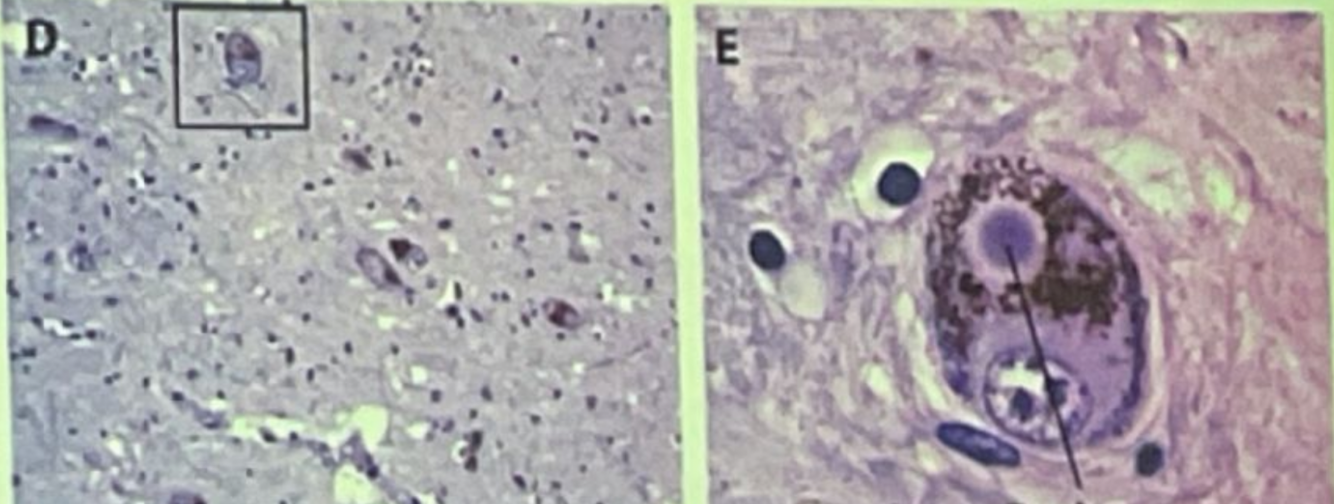

¿Que es esto?

Paciente con enfermedad de parkinson (cuerpos de lewy a la derecha)

Esta imagen se da en pacientes:

1